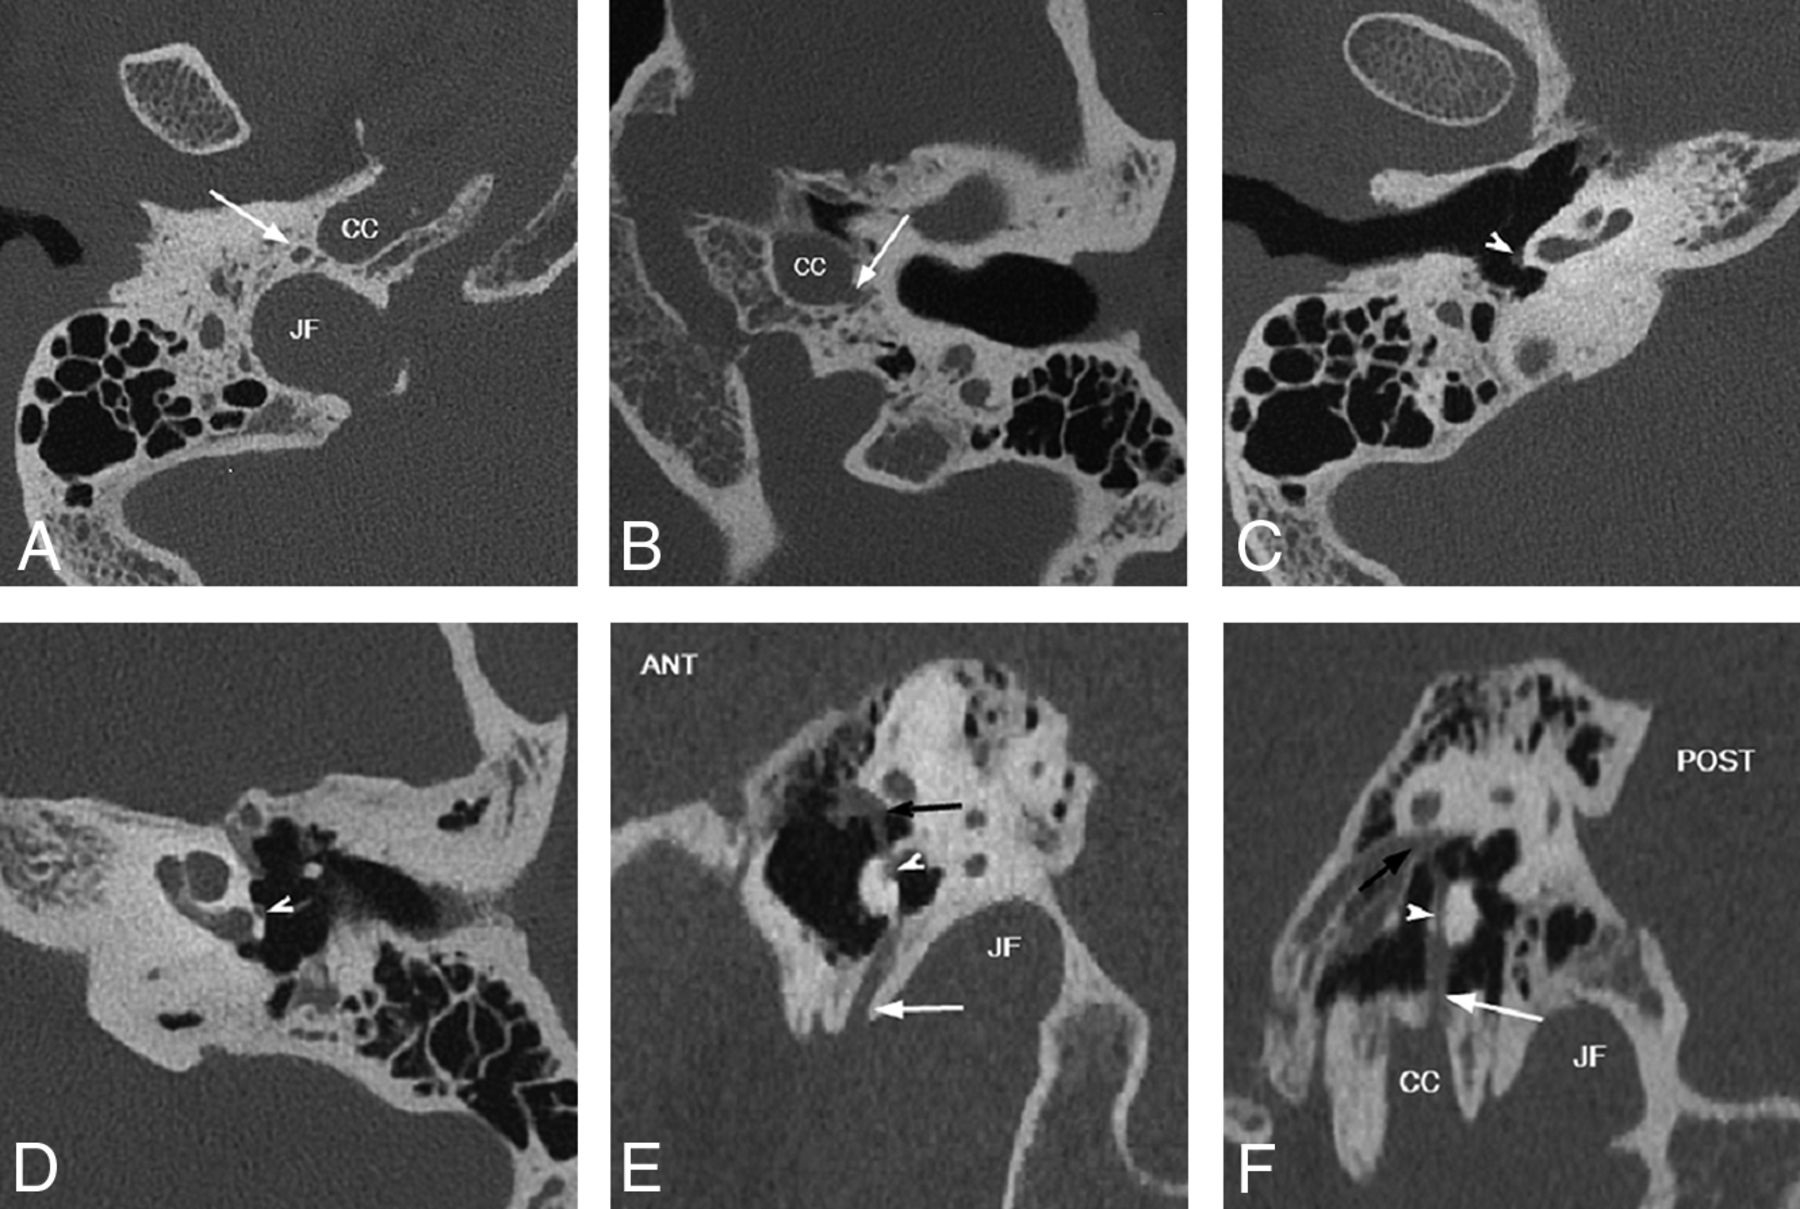

In both sagittal and coronal planes, the vertically oriented proximal PSA can be observed as a thin linear soft tissue attenuation coursing over the cochlear promontory after emerging from its bony channel (either the inferior tympanic or caroticotympanic canaliculi), referred to as the “string sign” (Fig 6). The trajectory of the “string” varies by subtype, with the pharyngostapedial artery (from the ITA) coursing along the posterior surface just anterior to the round window niche and the hyoidostapedial artery (from the CTA) taking a more anterior course (Fig 7). This sign was observed in all 10 PSA cases (100%) in our series.

Coronal oblique CT reconstructions demonstrate PSA coursing over the lateral surface of the cochlear promontory (string sign). Right PSA (A) arises from the inferior tympanic canaliculus (arrow), and left PSA (B) takes its origin from the carotid canal via caroticotympanic canaliculus (arrow), both traversing cephalad over the cochlear promontory (arrowheads). CC = carotid canal; JF = jugular foramen.

Variable origin of the PSA. Axial (A–D) and sagittal oblique (E and F) CT reconstructions. In A, C, and E, PSA arises from the ITC posterolateral to the carotid canal (CC) and anterior to the jugular foramen (JF), (white arrows). In B, D, and F, PSA arises directly from CC via CTC (white arrows). Note the posterior position of the PSA on the cochlear promontory with ITC origin versus the anterior position with CTC origin (white arrowheads), best seen on sagittal reconstructions, E and F, PSA traverses oval window niche to enter tympanic segment of the facial nerve canal (black arrows). ANT = anterior; POST = posterior.